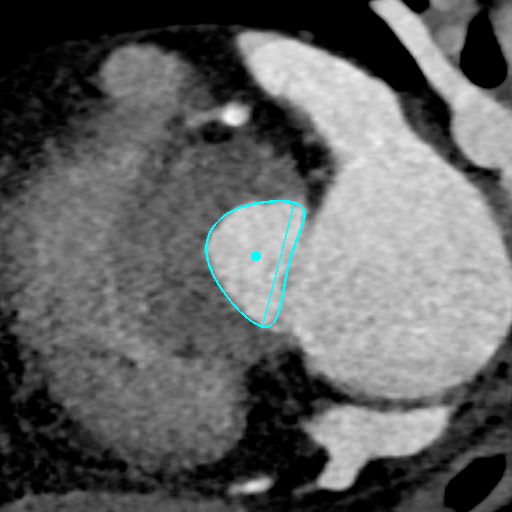

主动脉CT

主动脉瓣环平均直径:22.1mm;

左室流出道平均直径:23.7;

左冠脉开口:12.3mm;

右冠脉开口高度:11.2mm。

术前讨论:患者为三叶瓣主狭,左右冠瓣叶长,开口低,瓦氏窦小,左右冠高风险。

袁义强院长总结了该病例特点:三叶瓣,左右冠均高风险,解剖适合TAVR,年龄73岁,存在明确TAVR手术适应症。选择右股动脉入路,根据CT测量分析选择瓣膜大小,窦部情况可,瓣环平均直径22.1mm,计划22号球囊预扩,评估冠脉风险,选择植入24mm瓣膜。

右股动脉入路、22球囊扩张,植入24型号瓣膜;

监护麻醉,经右侧股动脉全麻行TAVR,选用22mm球囊扩张,查看冠脉风险,VitaFlow24瓣膜植入。